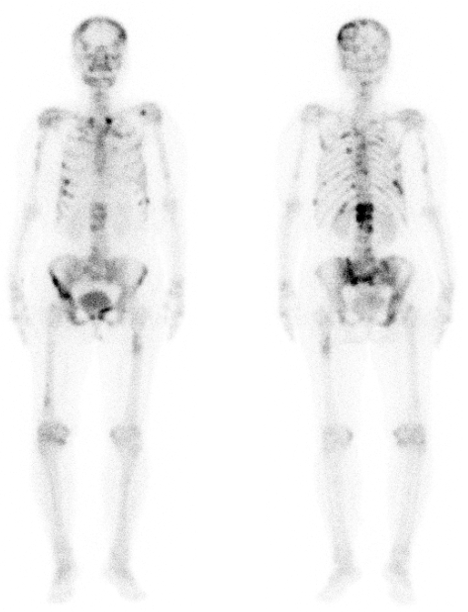

图例1:患者,女,54岁,左侧乳腺癌术前,行全身骨扫描发现全身多发骨转移。